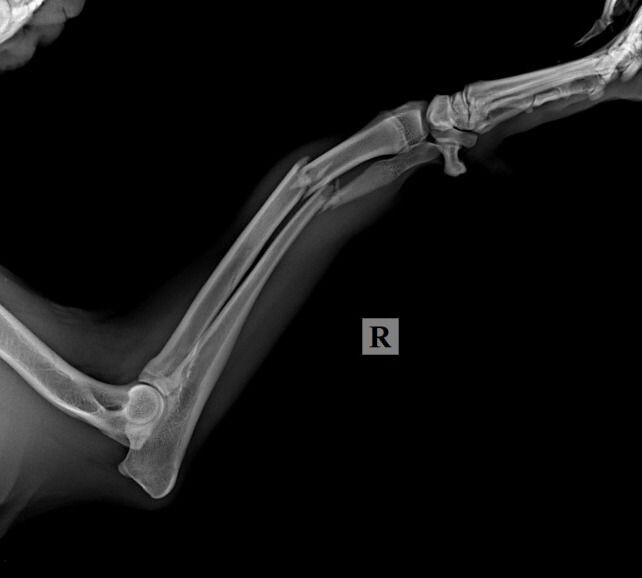

Осталось разобраться с самым главным,- у Кая полиtравма, переLом лучшевой кости, РПКС справа, выvих латеральный надколенника справа. Стоимость двух опер (оsтеосинтез) 104 300 рублей (2 опер). На одну опер мы собрали, завтра утром Кай будет проопер., а на вторую опер денег ни копейки НЕТ…